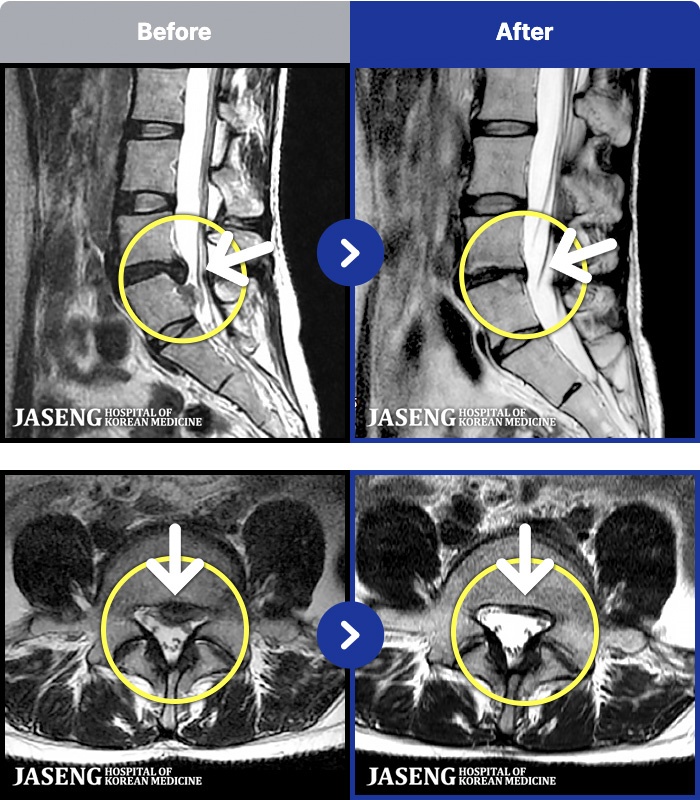

[뱸] 19.11.28~25.05.06

ȯںп Ǹ ǿ ԿǾ, ο ġ ۿ Ƿ ġḦ Ͻñ ٶϴ.